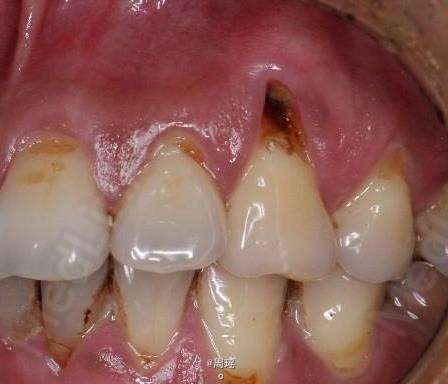

楔状缺损的充填

树脂修补

随访 讨论

效果很好,患者满意。